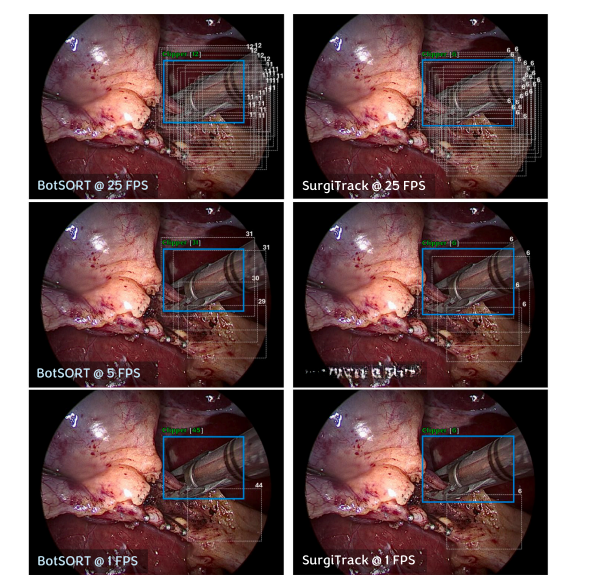

Fig. 4. Impact of direction estimation in tracking surgical tools at varying video sampling rates (i.e. 1, 5, 25 frames per seconds FPS). A demonstration is included in the qualitativevideo.

图 4. 方向估计在不同视频采样率(即 1、5 和 25 帧每秒 FPS)下对手术器械跟踪的影响。定性视频中包含演示。

Fig. 7. Qualitative result of SurgiTrack in comparison with a state of the art method (BotSORT) on tracking across variable frame rates (1FPS, 5FPS and 25FPS). Tick bluebounding box represents tool detection at current time. dotted gray bounding boxes detection at previous times, tool name represents tool classification, track identity number is written above each box. A demo is included in the qualitative results video.

图 7. SurgiTrack 与最先进方法 BotSORT 在不同帧率(1FPS、5FPS 和 25FPS)下进行跟踪的定性比较结果。 粗蓝色边框表示当前时间的器械检测,灰色虚线边框表示之前时间点的检测,器械名称表示器械分类,每个框上方标注轨迹身份编号。 定性结果视频中包含演示。